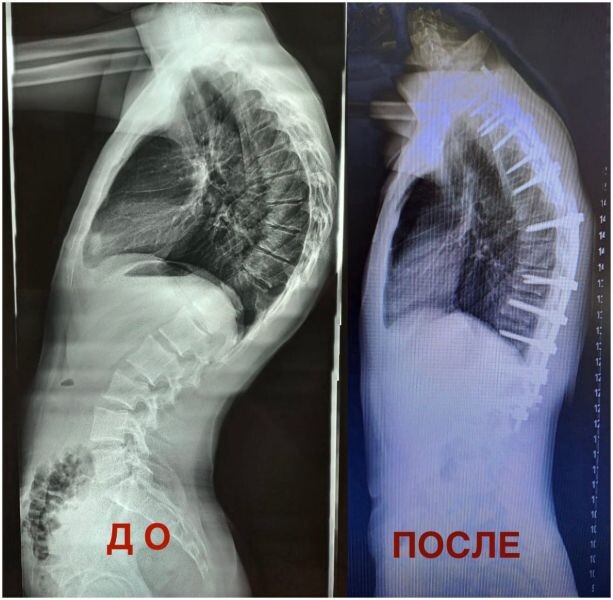

Консервативное лечение ребёнку не помогло Сложнейшую операцию на позвоночнике сделали 17-летнему пациенту из Воронежа с болезнью Шейермана-Мау, сообщил региональный минздрав. При этом недуге грудной отдел позвоночника сильно искривляется, что вызывает сильные боли. Мальчик получал консервативное лечение: ходил на массаж, лечебную физкультуру и физиотерапию, однако с годами состояние больного ухудшалось. В итоге искривление достигло крайней, четвёртой степени, и ребёнок стал испытывать постоянную боль. Нейрохирурги областной детской больницы № 2 решили провести пациенту операцию под названием остеотомия. В ходе вмешательства кость сломали и выровняли при помощи металлоконструкции. Сейчас подросток идёт на поправку и проходит курс реабилитации. Врачи отмечают, что состояние позвоночника больного значительно улучшилось.